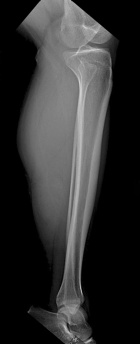

42 year old male presents with c/o L leg/calf pain that is worse with activity for the past year.